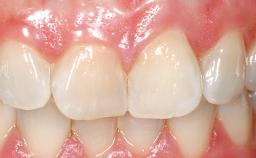

Immediate Flapless Placement of an Implant in a Maxillary Left Central Incisor Site

A 42-year-old female patient was referred to our clinic at the School of Dentistry of the University of São Paulo in November 2004, presenting a deficient restoration in the upper left central incisor. The clinical examination revealed no gingival retraction or any signs of gingival inflammation and, therefore, previous periodontal treatment was not considered. The patient presented a high lip line at full smile and a thin tissue biotype. This combination characterized a high-risk situation from an anatomic point of view, which required careful preoperative planning and cautious surgical execution.

Lip Line No exposure of papillae Exposure of papillae Full exposure of mucosa margin

Periodontal Phenotype Low-scalloped, thick Medium-scalloped, medium-thick High-scalloped, thin

Mesio-Distal Space Symmetry +/- 1 mm of contra-lateral tooth

Soft Tissue Contour and Volume Ideal